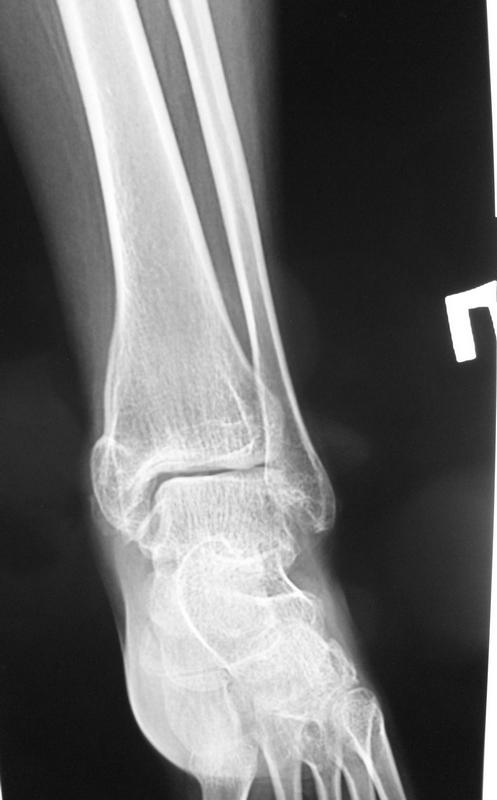

1.У пациентки перелом внутренней лодыжки сросся. Это видно из рентгенограмм. Болей нет.

> У пациентки перелом внутренней лодыжки сросся. Это видно из рентгенограмм. Болей нет.

Я вижу суперпозицию смещенной кпереди внутренней лодыжки и кортикальные замыкательные пластинки на центральном и периферическом отломках. Может сращение где-то на ограниченном участке и есть, но по имеющейся информации говорить об этом трудно. На данные КТ 2012г.!!! расчитывать не приходится.

> Эквинусная установка за счет переднего отдела.

наверное я слепой...

Наверное прежде чем планировать что-то хирургическое нужно получить правильные снимки. Здесь передне-задняя проекция видимо с наружной ротацией стопы. Хотелось бы глянуть на синдесмозную проекцию.

Меня больше всего смущает подвывих стопы кпереди. Возможно это связано с нерепонированной внутренней лодыжкой (ощущение, что она смещена кпереди).

Согласен. Типичная картина при плохо отрепонированной внутренней лодыжки.